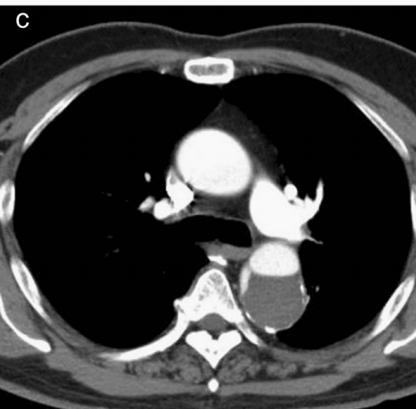

病例4

鲁迅说:孔乙己大约的确已经挂了!

下图的胸部CT平扫,基本上大约肯定可以看到一条线样阴影,将主动脉一分为二!

图10

增强CT一看,主动脉裂开了!

图11